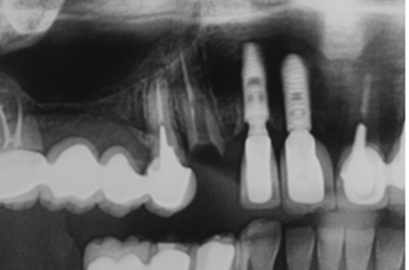

Na segunda consulta, a prótese parafusada metalfree foi instalada e aparafusada a 10 Ncm como recomendado pela fabricante. O orifício de acesso ao parafuso foi restaurado com resina fotopolimerizável e uma radiografia final foi realizada (Figuras 20, 21, 22 e 23).

Figura 23 – Imagem radiográfica comparando a adaptação da prótese parafusada do elemento 13 com a prótese cimentada do elemento 12, realizado anteriormente